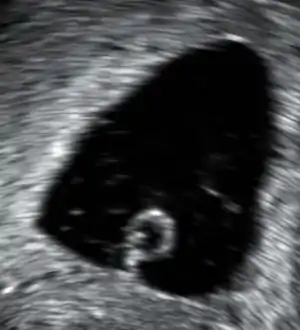

Transvaginal ultrasonography showing a gestational sac with a diameter of 28 mm, corresponding to a gestational age of approximately 7 weeks and 5 days. It contains a yolk sac (protruding from its lower part) but no embryo, even after scanning across all planes of the gestational sac, thus being diagnostic of an anembryonic gestation. | |

A blighted ovum or anembryonic gestation is characterized by a normal-appearing gestational sac, but the absence of an embryo.[2] It likely occurs as a result of early embryonic death with continued development of the trophoblast. When small, the sac cannot be distinguished from the early normal pregnancy, as there may be a yolk sac, though a fetal pole is not seen. In anembryonic pregnancy, levels of the pregnancy hormone human chorionic gonadotropin (hCG) typically rise for a time, which can cause positive pregnancy test results and pregnancy symptoms such as tender breasts.[2][7] Because of the presence of hCG, an ultrasound is typically necessary to diagnose an anembryonic pregnancy.[3] For diagnosis, the sac must be of sufficient size that the absence of normal embryonic elements is established. The criteria depends on the type of ultrasound exam performed. A transvaginal ultrasound provides a better view of early pregnancy than a transabdominal ultrasound.[8] Generally, a transvaginal ultrasound is used to investigate a suspected case of blighted ovum.[2][7] A pregnancy is anembryonic if a transvaginal ultrasound reveals a sac with a mean gestational sac diameter (MGD) greater than 25 mm and no yolk sac, or an MGD >25 mm with no embryo.[9] A transabdominal ultrasound can be used to diagnose anembryonic pregnancy if a gestational sac can be identified, but is empty.[3] An anembryonic pregnancy is never viable, as in viable pregnancy the embryo must form with the gestational sac.[2]